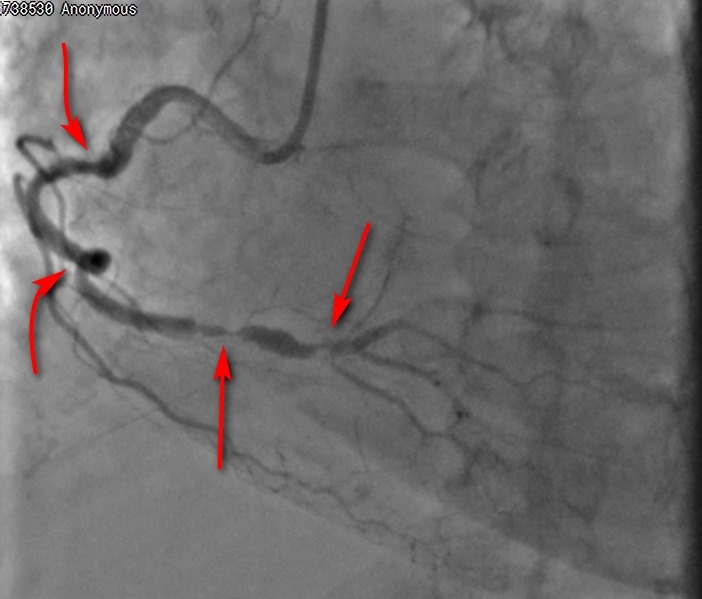

Один из показательных примеров. Пациентка с сахарным диабетом, обратилась с незаживающей язвой на стопе и болью (синдром диабетической стопы).

После обследования искренне удивилась, что у нее есть признаки поражения сосудов сердца – оно же ее не беспокоило. Мы получили объективные данные – ЭКГ, ЭХО-КГ, поэтому настояли и сделали коронарографию – исследование сосудов сердца. Все основные артерии, кровоснабжающие сердце, критически сужены (поражения показаны стрелками). Такой пациент имеет шансы умереть в любую минуту. Тем более – во время любого вмешательства или операции (в том числе – по время высокой ампутации, если такому пациенту она выполняется, что не редкость, к сожалению).